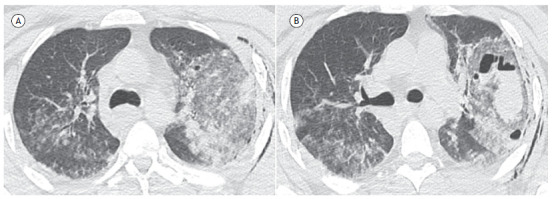

Pulmonary laceration.

肺裂伤。